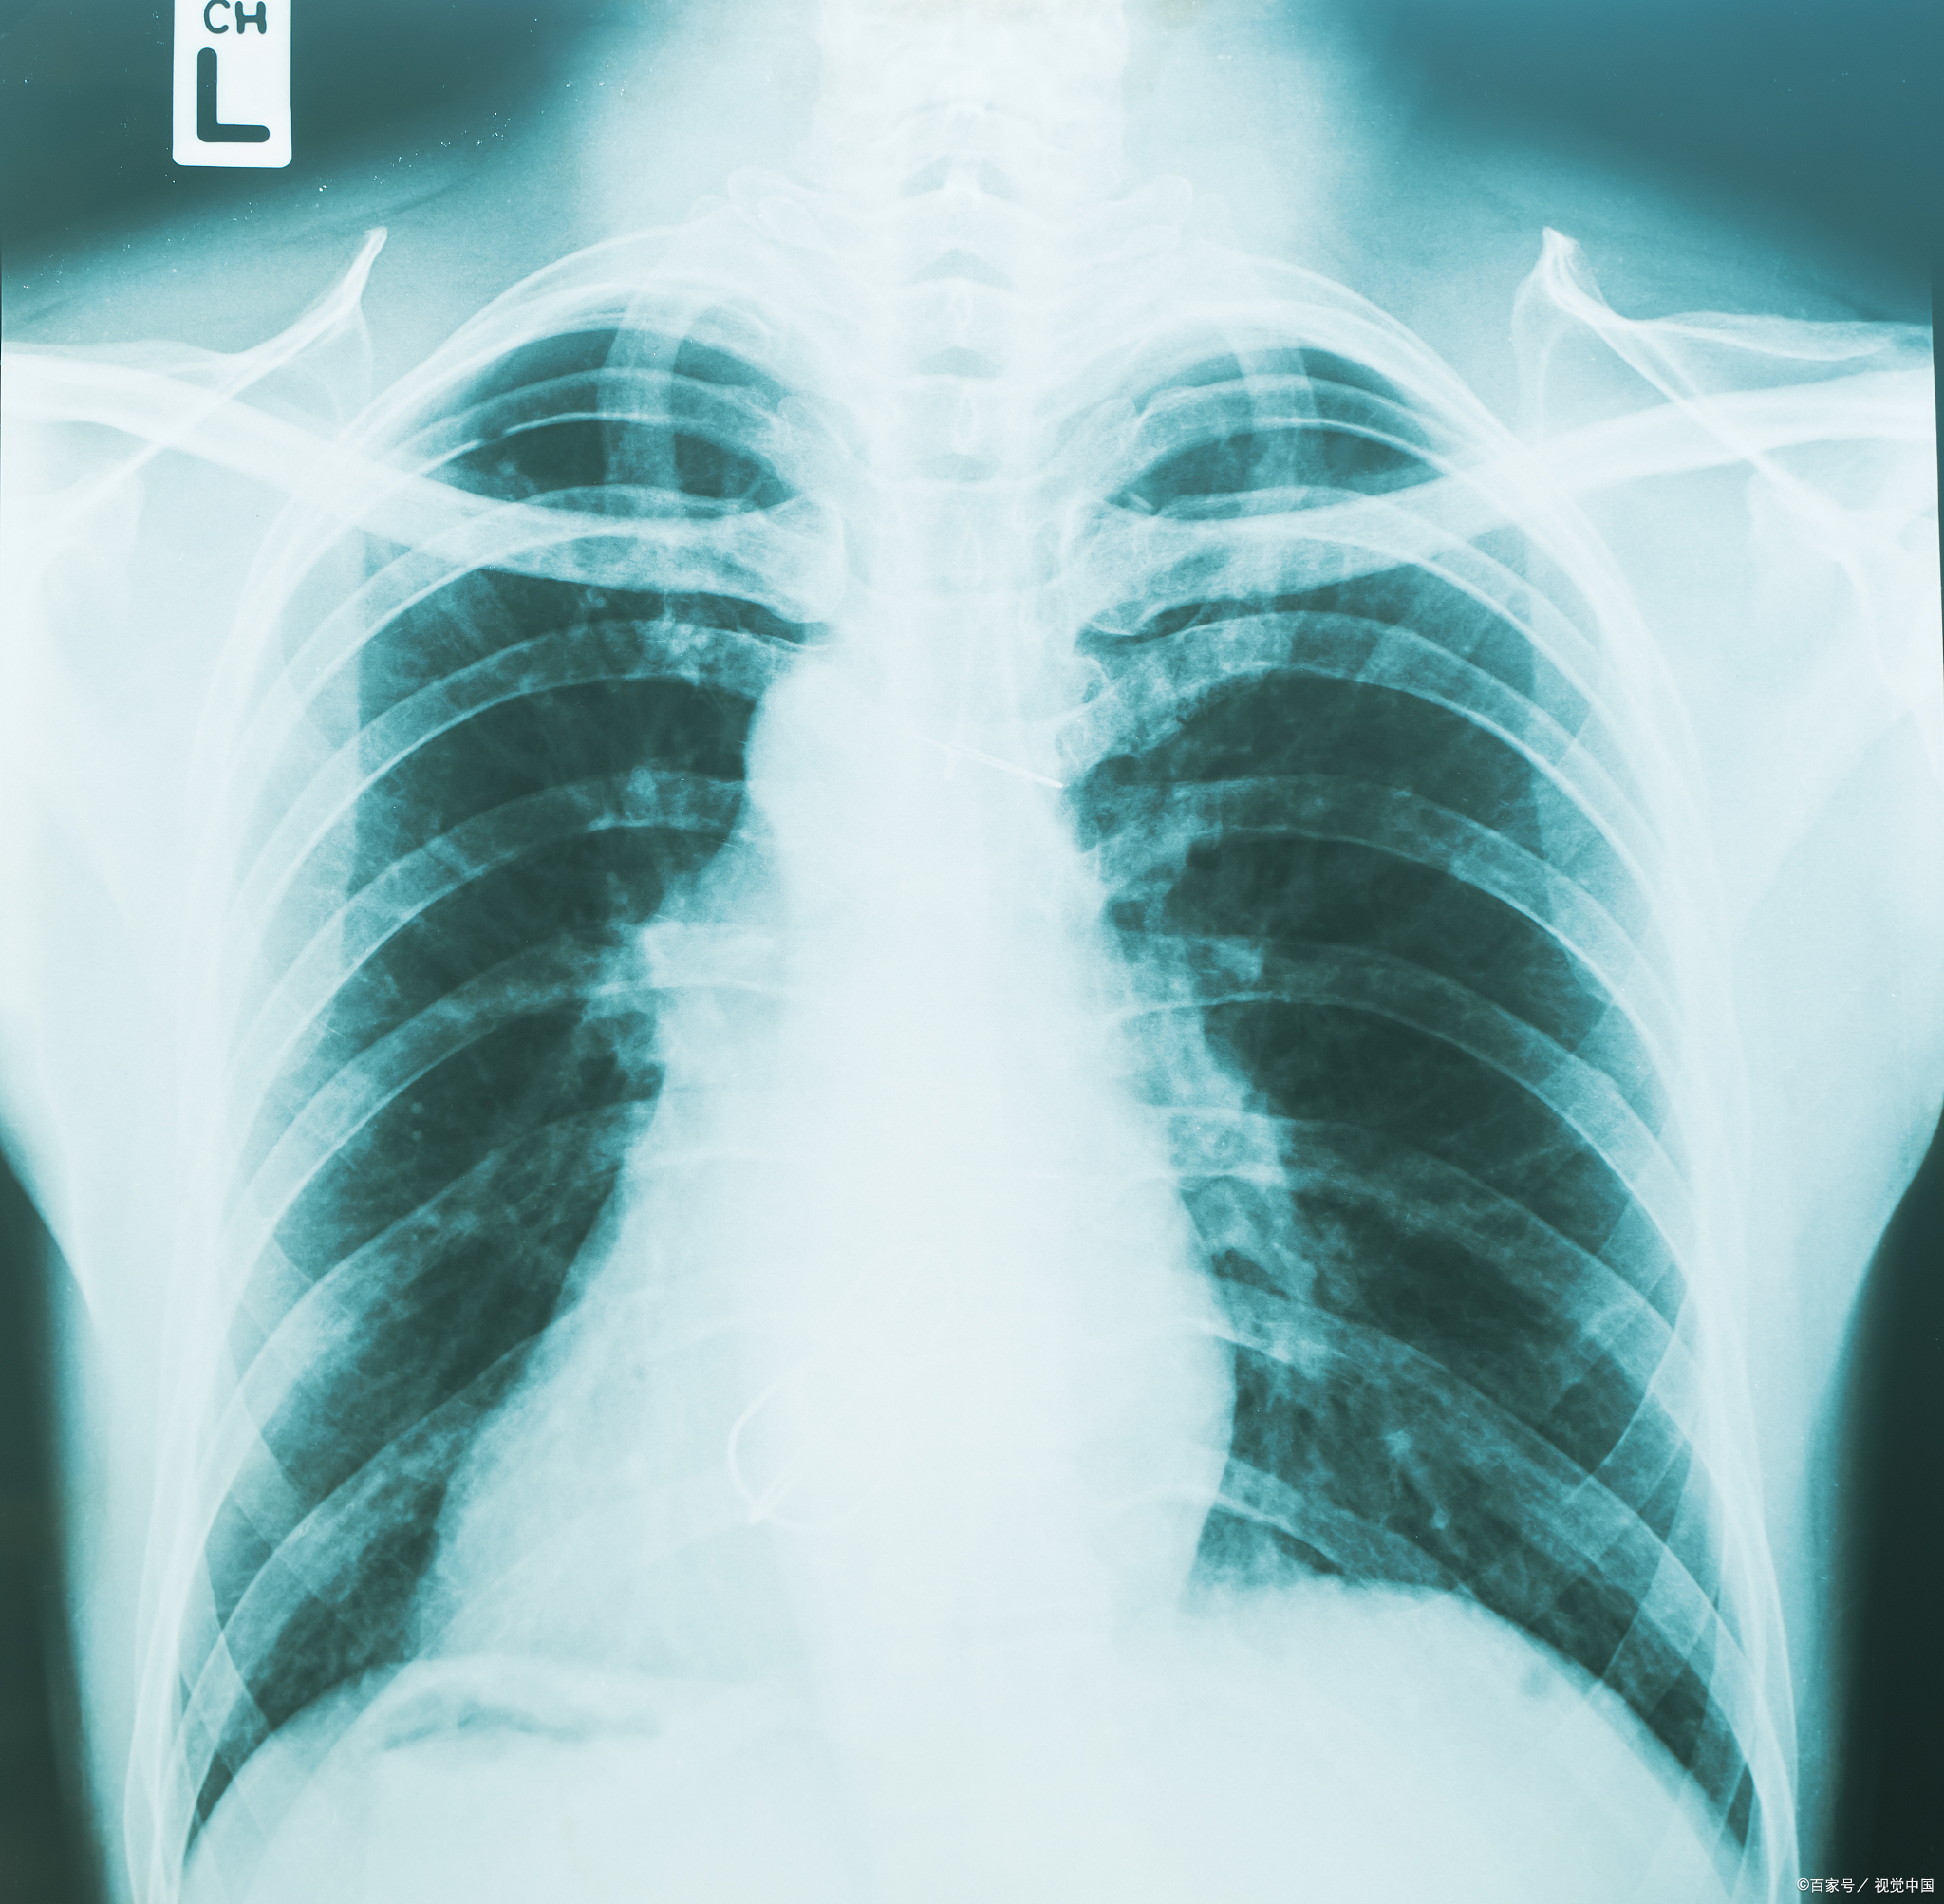

肺炎x光片表现

肺炎是呼吸系统常见疾病,而x光检查作为基础影像

一分钟教你看胸片,识别各种肺炎